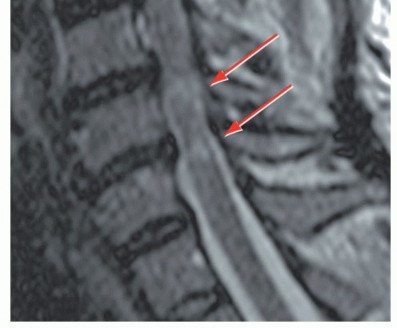

IMAGING AND OTHER DIAGNOSTIC STUDIES A lateral radiographic view can be helpful in showing the amount of congenital cervical stenosis as well as sagittal alignment. Lateral views are consistent with congenital stenosis when the ratio of the diameter of the canal to the diameter of the vertebral body is less than 0.8. Particularly if OPLL is suspected, computed tomography (CT) scans (with or without myelograms, depending on whether a high-quality magnetic resonance imaging [MRI] is available) are helpful in delineating bony versus soft tissue pathology. ## DIFFERENTIAL DIAGNOSIS Of cervical myelopathy Amyotrophic lateral sclerosis Myopathies Peripheral neuropathy Syringomyelia Multiple sclerosis Diabetic neuropathy Brachial plexopathy ## NONOPERATIVE MANAGEMENT Surgery is generally the treatment of choice for symptomatic cervical myelopathy. Nonoperative treatment of cervical myelopathy is typically reserved for patients who cannot tolerate surgery.4 Controversy exists regarding the management of patients with asymptomatic spinal cord compression. In those with severe asymptomatic compression, consideration should be given to prophylactic surgery, particularly if cord signal changes are present, to prevent spinal cord injury with trauma (eg, central cord syndrome) (FIG 2).

### FIG 2 • Sagittal T2-weighted MRI demonstrating spinal cord signal changes.